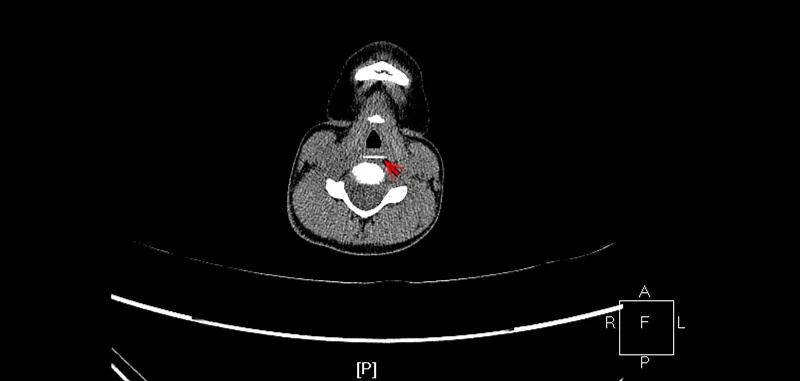

5小时余前食用瓜子后有可疑呛瓜子,后出现咳嗽伴气喘。位于气管分叉处,您还能看出瓜子君的本来面目吗?